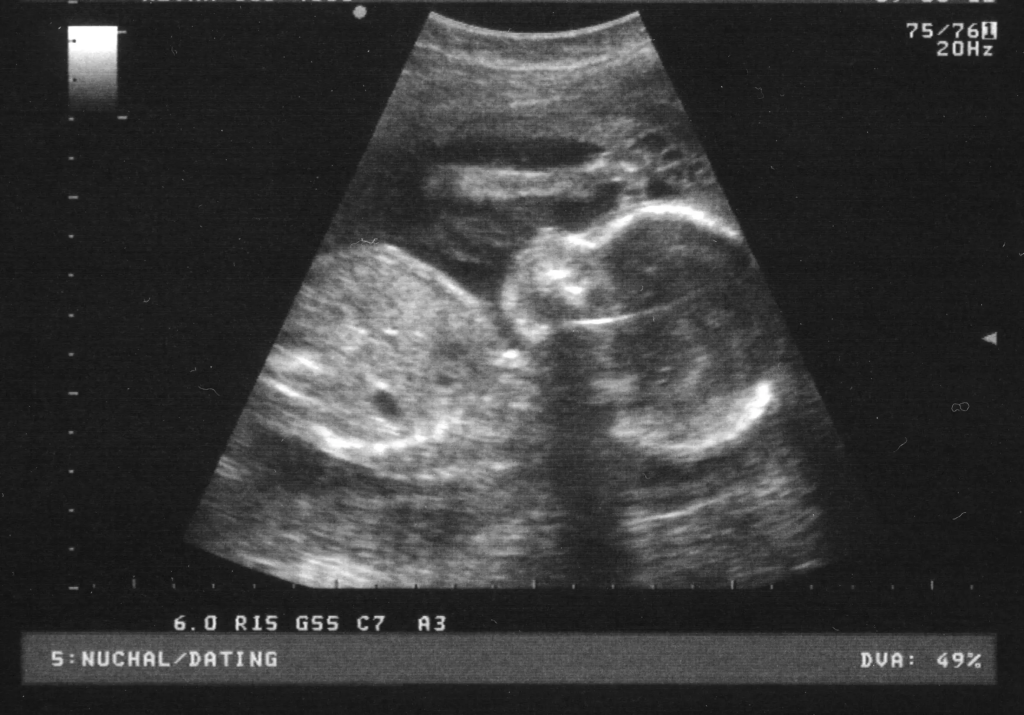

V naši ambulanti se vedno trudimo imeti čimbolj strokoven pristop. To lahko dosežemo le z nenehnim izobraževanjem in spremljanjem razvoja medicinskih postopkov doma ter v tujini. Tako smo se med drugim specializirali za različne preglede, kot je nuhalna svetlina Ptuj.